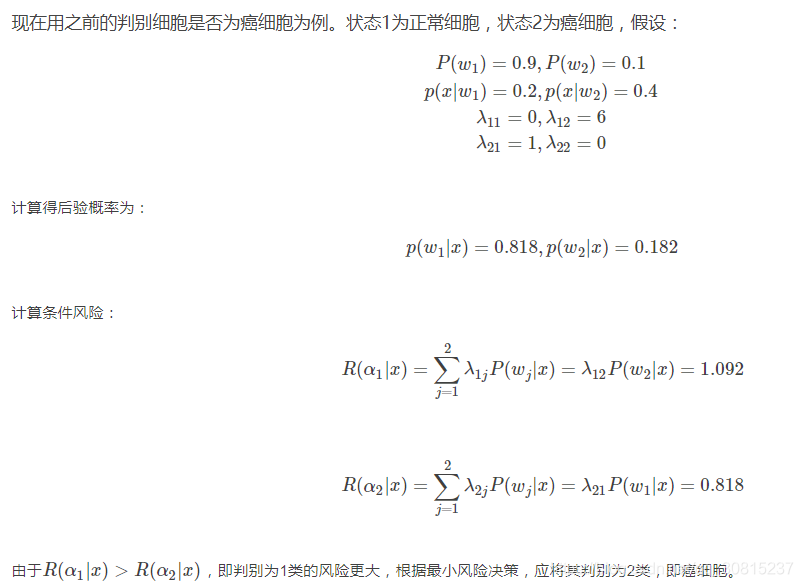

在决策中,除了关心决策的正确与否,有时我们更关心错误的决策将带来的损失。比如在判断细胞是否为癌细胞的决策中,若把正常细胞判定为癌细胞,将会增加患者的负担和不必要的治疗,但若把癌细胞判定为正常细胞,将会导致患者失去宝贵的发现和治疗癌症的机会,甚至会影响患者的生命。这两种类型的决策错误所产生的代价是不同的。

考虑各种错误造成损失不同时的一种最优决策,就是所谓的最小风险贝叶斯决策。设对于实际状态为wj的向量x采取决策αi所带来的损失为![]()

该函数称为损失函数,通常它可以用表格的形式给出,叫做决策表。需要知道,最小风险贝叶斯决策中的决策表是需要人为确定的,决策表不同会导致决策结果的不同,因此在实际应用中,需要认真分析所研究问题的内在特点和分类目的,与应用领域的专家共同设计出适当的决策表,才能保证模式识别发挥有效的作用。

对于一个实际问题,对于样本xx,最小风险贝叶斯决策的计算步骤如下:

(1)利用贝叶斯公式计算后验概率:

其中要求先验概率和类条件概率已知。

(2)利用决策表,计算条件风险:

(3)决策:选择风险最小的决策,即:

![]()

由此可见,因为对两类错误带来的风险的认识不同,从而产生了与之前不同的决策。显然,但对不同类判决的错误风险一致时,最小风险贝叶斯决策就转化成最小错误率贝叶斯决策。最小错误贝叶斯决策可以看成是最小风险贝叶斯决策的一个特例。